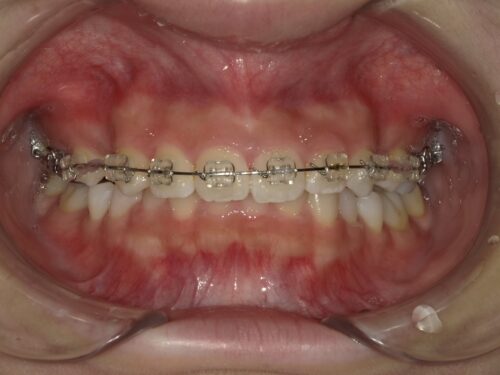

ワイヤー装着後・正面の写真

正面から見た、ワイヤーを装着した状態です。ここからいよいよ歯が動き始めます。